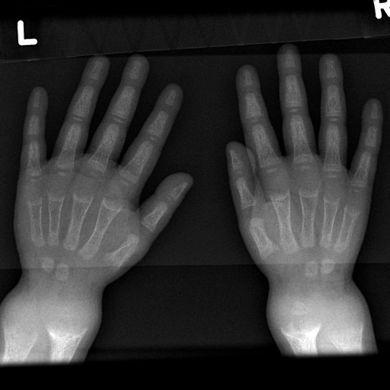

- يظهر التصوير الشعاعي عادة اتساع مناطق التكلس المؤقت للكراديس الثانوية للعظم غير المعدني. عادة ما تظهر التجلف ، والابلاء ، والتفلطح في الكراديس مع النمو وتحمل الوزن المستمر.[37] تُرى هذه التغييرات في الغالب في مواقع النمو السريع ، بما في ذلك عظم العضد القريب ، والزند البعيد ، وعظم الفخذ البعيدة وكل من الظنبوب الداني والبعيدة. لذلك ، يمكن إجراء مسح للهيكل العظمي للكساح باستخدام الصور الشعاعية الأمامية الخلفية للركبتين والمعصمين والكاحلين.[37]